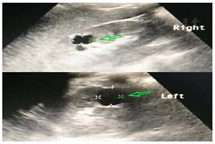

患者男性,30岁,以"多饮、多尿14年,肢体麻木1个月"入院。确诊糖尿病14年,一直予以"诺和灵50R"降糖,平素未监测血糖,亦未定期医院随访。患者已婚,已育1子1女,患者父母及子女无疾病表征。体格检查:身高173 cm,体重57 kg,体重指数(BMI)19.04 kg/m2。发育正常,体型偏瘦,肝脾肋下未触及,双肾区叩击痛阴性,四肢活动正常。辅助检查:随机静脉血糖23.0 mmol/L,血酮体阳性,二氧化碳结合力40.1,肾功能正常;肝功能:谷草转氨酶41.9 U/L(正常参考范围15~40 U/L,下同),血脂及电解质正常,HbA1C17.5%(4.8%~6%),尿白蛋白/肌酐比值(ACR)107.4 mg/g(0~30 mg/g),24 h尿蛋白定量0.15 g(0~0.5 g),甲状腺功能及相关抗体阴性,自身抗体全套阴性,C肽释放试验:空腹C肽0.17 pmol/L,30 min C肽0.13 pmol/L,60 min C肽0.17 pmol/L,120 min C肽0.14 pmol/L,180 min C肽0.20 pmol/L,胰岛素抗体阴性,抗谷氨酸脱羧酶抗体阴性。腹部及泌尿系彩超:双肾囊肿(图1)。眼科检查:双眼底未见明显渗出及出血。3个月后随访复查尿ACR 105.6 mg/g,HbA1C 9.3%,空腹指尖血糖波动在6.0~9.0 mmol/L,餐后2 h指尖血糖波动在9.0~10.0 mmol/L。

注:绿色箭头指明肾脏囊肿部位